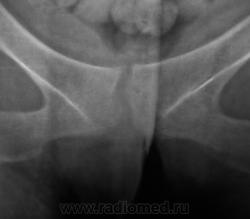

Из анамнеза известно, что примерно 2 месяца тому "летела" со сноутборга около 200 метров. Сейчас беспокоят боли в области спины, крестца и лонного сочленения. УЗИ было сделано всего, что только можно, везде - "норма". Хирурги, вроде-бы тоже ничего не находят. Но боли, видать значительные, походка вынужденная. На рентгенографию была направлена, как жест отчаяния, мол может быть, что-то найдут.

1. Не исключаю поперечный перелом S5.

2. Лонное сочленение очевидно,подверглось значительному растяжению (имеется локальный вакуум-феномен слева), умеренно выраженые явления симфизита (опять же - постравматического).

1. По первым снимкам не отпускало впечатление о повреждении левого крестцово-подвздошного сочленения. После подготовки вроде-бы все нормально, но все равно что-то гложет.

Возможно, перелом последнего копчикового тоже был?

Поздно заметил ветку.. увидел симфизит, перелом остистого L4, мазоль Co 5, и  конечно spina bifida S1 ))) глянуть бы межпозвоночные..